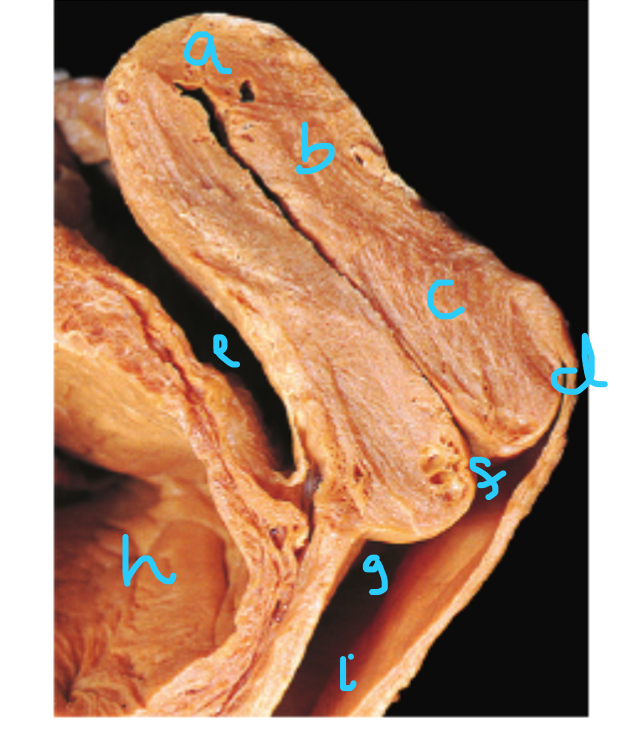

What muscle is pinned?

Ischiocavernosum